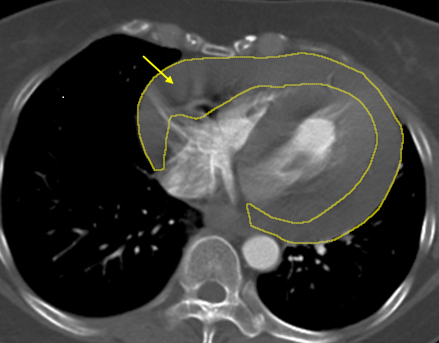

▲大量血液積聚於心包膜內(黃圈處),對心臟造成壓迫,未及時處置恐危及生命。(圖/土城醫院提供)

收治個案的土城長庚醫院胸腔及心臟血管外科主治醫師鄭元熙說明,心包積血是指血液在極短時間內大量堆積於心臟外層空間,造成心臟受壓,無法正常擴張與跳動,血壓會急遽下降,甚至在數分鐘內引發心跳停止,是典型的立即致命急症;而升主動脈為全身最粗大的血管,一旦發生剝離或破裂,出血速度宛如水管爆裂,臨床上不乏患者在尚未送醫前即發生致命後果。

陳小姐回憶自己長期有反覆頭暈的困擾,過去也曾因突發頭暈騎腳踏車摔倒,但因症狀短暫而未進一步就醫檢查,此次休克後,影像檢查確認為大量心包積血。醫療團隊第一時間成立跨科搶救小組,由心臟外科緊急執行「劍突下心包開窗術」,迅速解除心臟壓迫、穩定循環,隨後無縫銜接由血管外科進行高難度的「升主動脈置換術」,以人工血管重建破裂的主動脈。